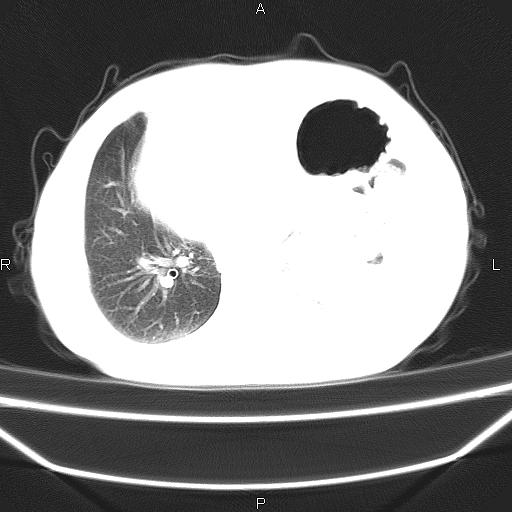

患者,男。50岁。近几日有咳嗽症状,无其他不适,既往病史无,考虑膈疝。请前辈们看看指导指导。

膈膨升,左下肺通气不良,膈肌好像还完整。

考虑左侧膈疝。

左侧膈疝。

符合隔膨升,膈肌较完整。